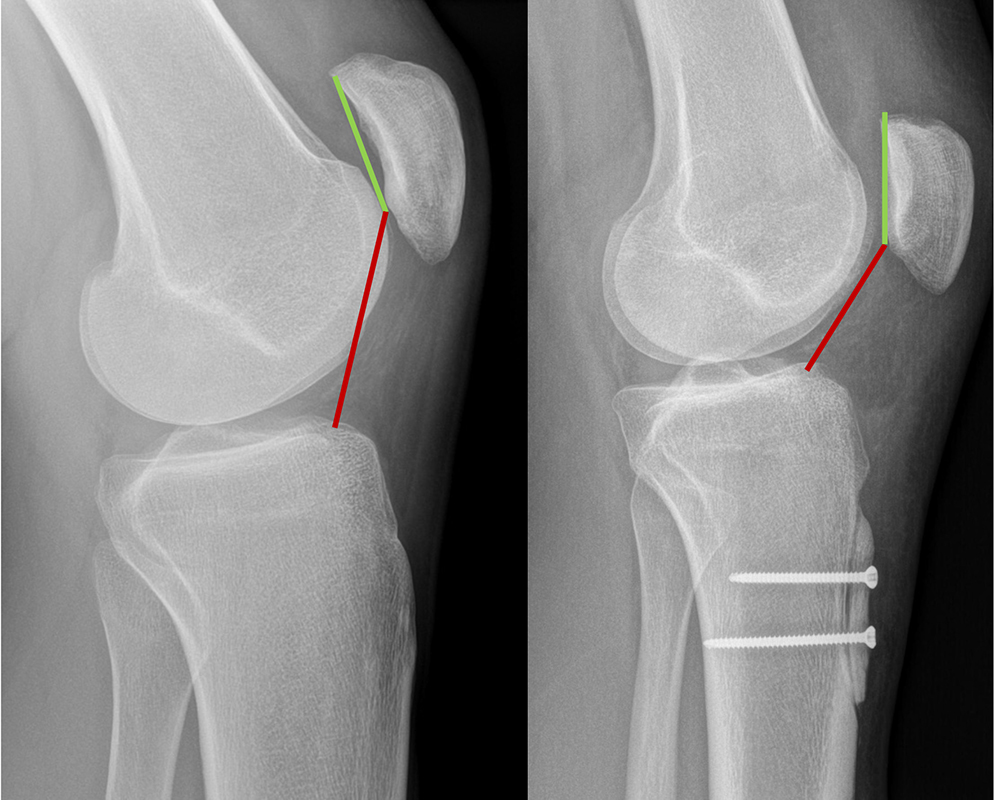

2. Hochstehende Patella

Steht die Patella „zu hoch“, gleitet sie erst spät in die Trochlea ein. Dadurch fehlt in den ersten Beugegraden die knöcherne Führung – genau dort passieren viele Luxationen. Bei deutlichem Patellahochstand kann ein nach unten Versetzen des Kniescheibensehnenansatzes die Kniescheibe stabilisieren.

Bildgebung ist mehr als nur ein MRT

Für die Therapieplanung braucht es eine saubere Risikoanalyse: klinische Tests plus Bildgebung. Röntgen, MRT und ggf. CT helfen, die „Treiber“ zu identifizieren – genau das ist die Grundlage des individualisierten Therapieansatzes.

2. Versetzung des Patellasehnenansatzes

Indiziert bei deutlicher Lateralisierung und/oder Patellahochstand, ggf. auch zur Lastumverteilung bei Knorpelschäden. Das Ziel ist eine günstigere Zuglinie und frühere, stabilere Führung der Patella.